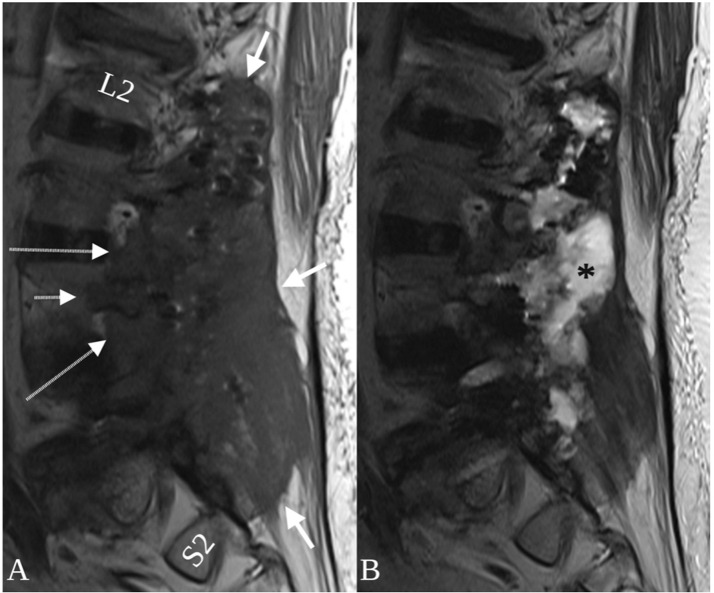

Fig. 2.

Trans-spatial involvement of a paraspinal metalloma. On the T1-weighted image, a mass (A, thick arrows) is present in the paraspinal soft tissues surrounding a paraspinal rod. The T1 hypointense signal abnormality extends into the marrow spaces of the adjacent iliac bone (A, short thin arrow) and sacrum (A, long thin arrow) and the epidural space (A, asterisk). No lytic or sclerotic changes are present on the corresponding CT performed 3 days later (B, arrows).

Sagittal T1 (A) and T2-weighted MRI (B) following resection of the metalloma and hardware explantation. The lesion is longitudinally extensive, spanning the paraspinal space of L2-S2 (A, thick arrows) with extension into neural foramina (A, long arrows) and a pedicle (A, short arrow). A T2 hyperintense post-operative fluid collection occupies the resection cavity (B, asterisk) and pedicle screw removal sites.

Descriptions in the literature of imaging findings of spinal fusion-related metallosis and pseudotumors and/or metallomas are scant. This is likely due to rarity and due to hardware-related artifact that often obscures the region of interest on CT and MR images. Fortunately, in the case presented here, the large metalloma size allowed accurate characterization of the lesion on MR imaging. The metalloma in this case was a unique mix of both benign and aggressive imaging features. Trans-spatial involvement is a feature most commonly observed in aggressive processes such as malignancy and infection. In the featured case, the lesion was centered around the fusion construct in the paraspinal space and the associated T1 hypointense signal abnormality extended into adjacent bones (pedicles, iliac bone, sacrum) and soft tissues (epidural space, extraforaminal space, retroperitoneal space and/or psoas muscle), with seemingly no hinderance posed by the fascial planes that normally separate theses spaces (Fig. 1, Fig. 2). Mass effect is another feature concerning for an aggressive process that was seen in this case. However, the lesion appeared completely non–enhancing on post-contrast T1-weighted imaging – a feature more commonly associated with non–aggressive processes (Fig. 1). The combination of trans-spatial involvement and lack of contrast-enhancement may be a finding unique to metallomas. Additional imaging clues to the diagnosis in this case are the location of the lesion, which surrounded the fusion construct, and the T1 and T2 isointensity to skeletal muscle, which has been described with metallosis and pseudotumors involving metal-on-metal hip arthroplasties and may be related to T2 gradient recalled echo (T2 GRE or T2*-weighted imaging) effects of small metal particles [37].